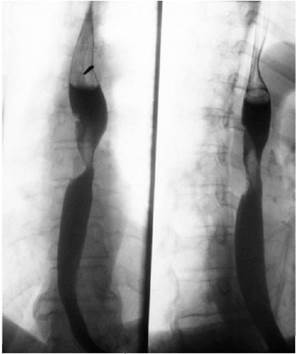

У больного с травмой грудной клетки на рентгенографии обнаружена следующая картина.  Назовите полный диагноз//

Назовите полный диагноз//

Перелом 4-5 ребер, пневмоторакс справа//

Перелом 7-8 ребер, гемоторакс справа //

+Перелом 7-8 ребер, гемопневмоторакс справа//

Перелом 4-5 ребер, гемоперикард справа//

Перелом 6-7 ребер, нижнедолевая пневмония справа